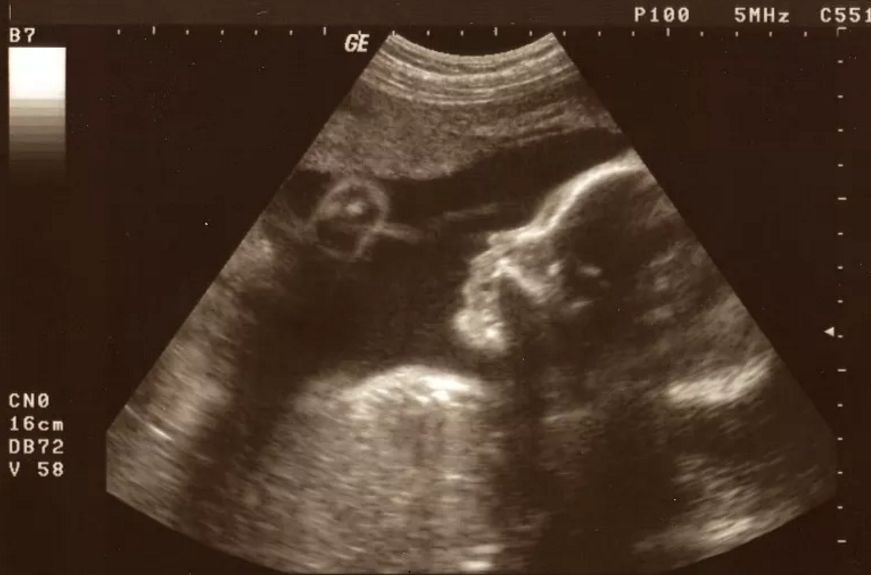

研究显示,胎儿的性反应能力在受孕后不久就已经存在,如早在1982年的一张超声波摄像图显示,男性胎儿在子宫里就会出现有规律的阴茎勃起现象。女婴的性唤起现象虽不易察觉,但性反应从出生后不久就开始了,如阴道湿润和生殖器官胀大。